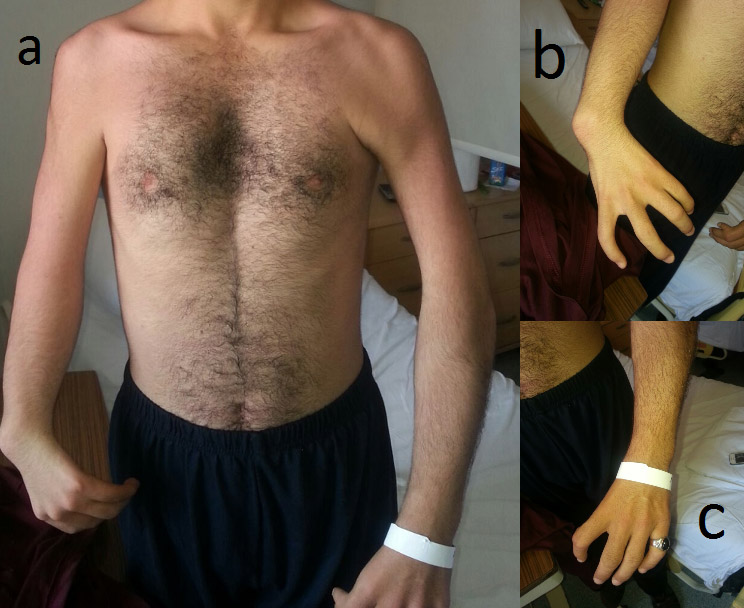

A 20-year-old male patient presented with HOS. He had no thumb on either hand and a pectus excavatum deformity (Figure 1). An ASD and mild aortic valve insufficiency were observed on echocardiography. Surgery was indicated due to substantial shunting, which may lead to volume overload of the right atrium, right ventricle, and pulmonary arteries.

The patient was extubated six hours postoperatively, taken to the regular hospital unit on the first postoperatıve day, and discharged to home on the eighth postoperative day. After one year, the wound healing was perfect (Figure 3).